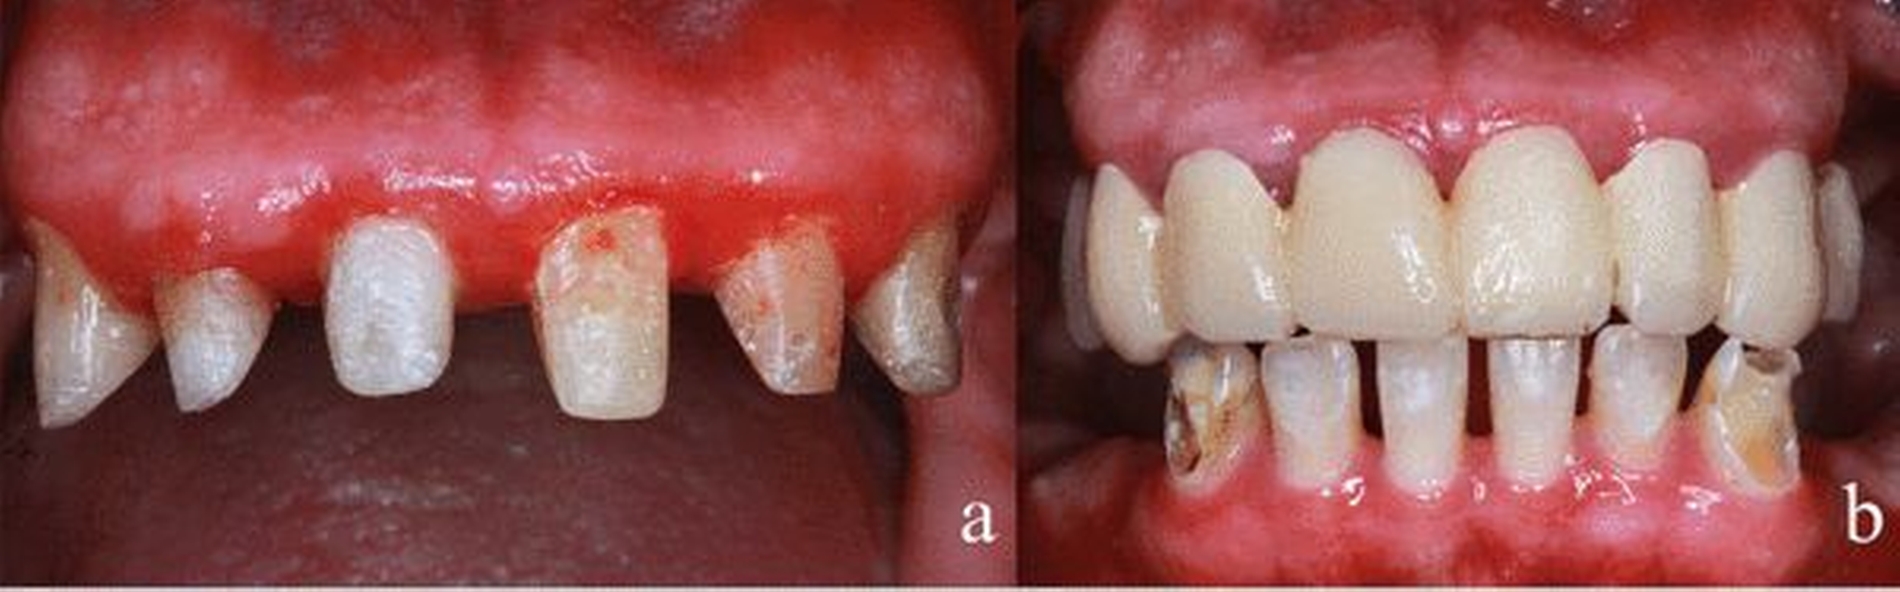

Aufgrund der massiven Beläge an der Restbezahnung erfolgte zuerst eine professionelle Zahnreinigung von Ober- und Unterkiefer. Anschließend wurde die chirurgische Sanierung in ITN durchgeführt. In dieser Sitzung wurden die Zähne 18–14, 28–24, 38–34 und 48–44 extrahiert. An den darauffolgenden Terminen erfolgte in Lokalanästhesie die endodontische Therapie der Zähne 12, 11 und 23 sowie die Stumpfaufbauten an diesen Zähnen (Abbildung 3a). Die Zähne im Unterkiefer konnten mit konservierenden Maßnahmen erhalten werden. Der Patient wurde zwischenzeitlich mit einem festen Provisorium im Oberkiefer versorgt (Abbildung 3b). Nach der chirurgischen Sanierung war eine gestiegene Motivation des Patienten feststellbar, die sich auch in einer verbesserten Mundhygiene ausdrückte.